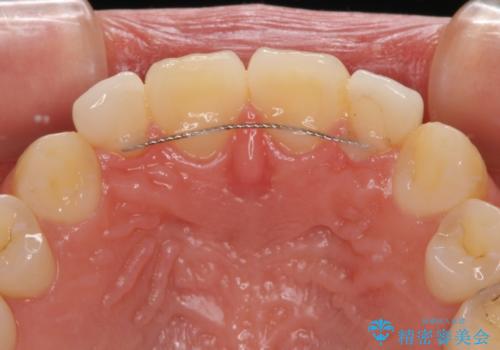

着色の原因として、湿気の多い環境で接着操作を行うと、境目に細かいギャップができてしまうことが考えられます。

接着の際にはラバーダムを使用して、乾燥した環境を整えて処置を行いました。